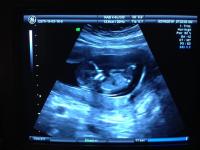

@caroline4: tényleg senki nem mondaná meg, hogy már 3 gyerkőcöd van! én is ilyen szeretnék lenni 10 év múlva, legalább ennyi gyerekkel ![]()